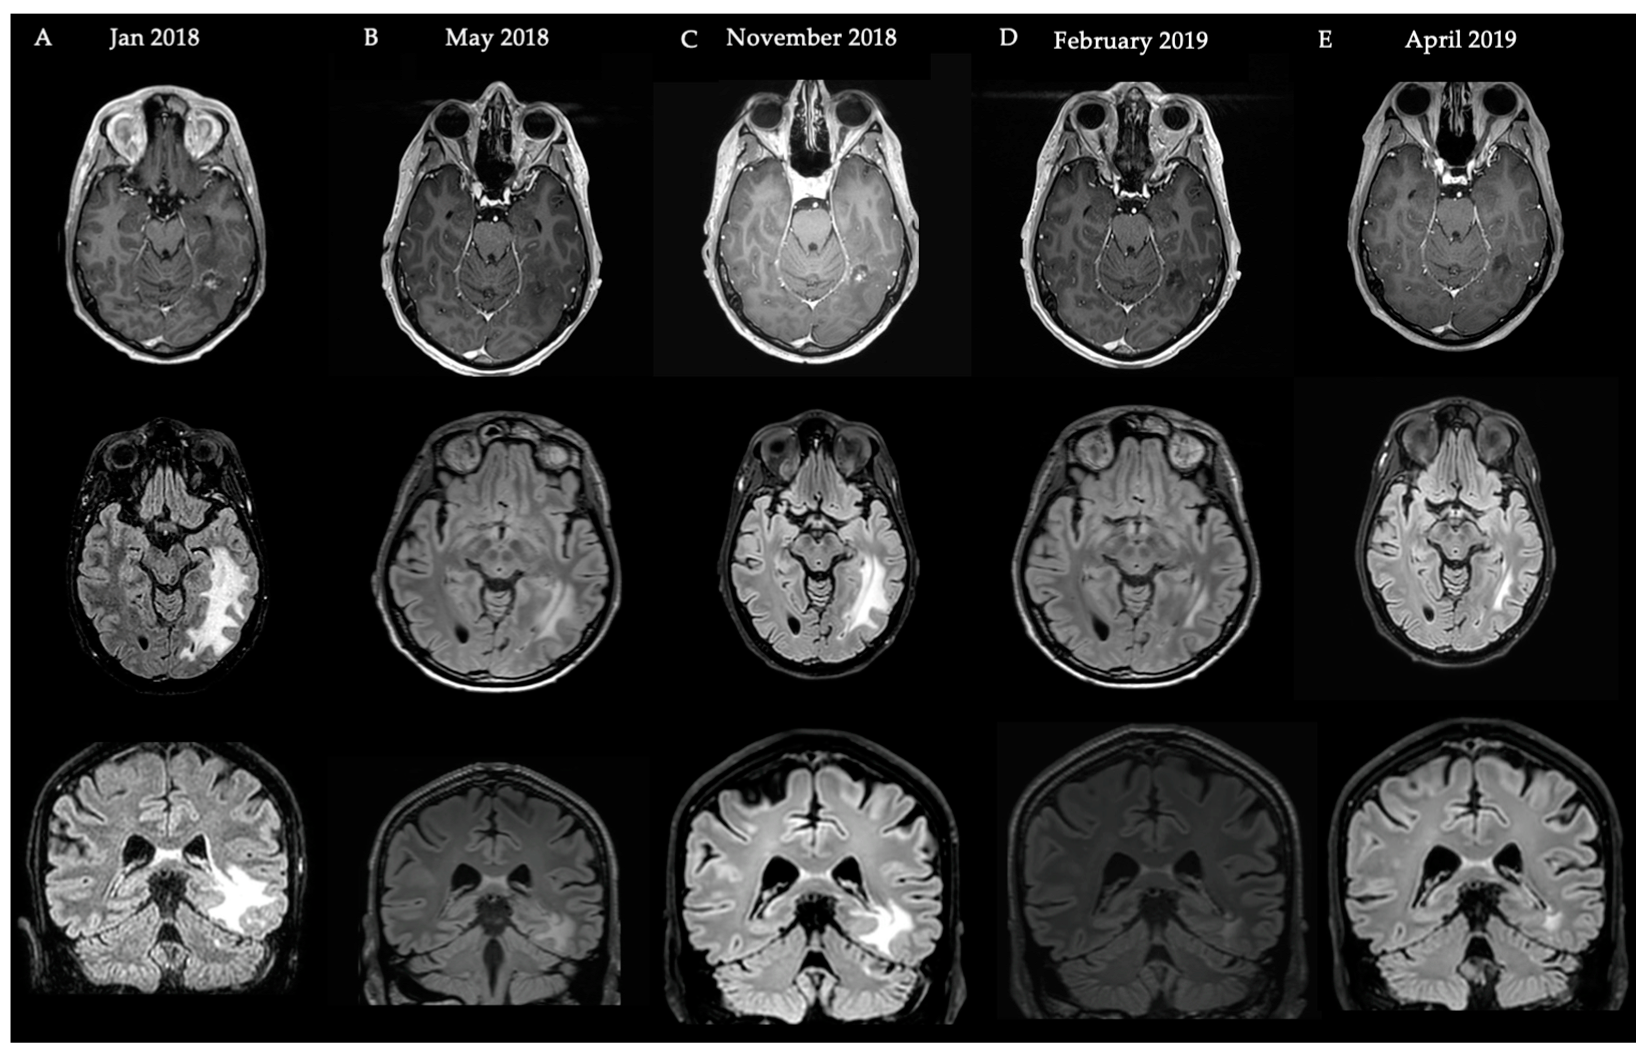

4.2. Case Illustration 2